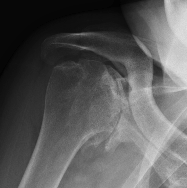

Levigne and Franceschi Classification

Three main patterns

| Type 1 | Type 2 | Type 3 |

|---|---|---|

|

Upward migration Superior glenoid wear |

Concentric medial migration Deficient medial bone stock |

Destructive |

Due to rotator cuff insufficiency Most common pattern |

||

Medial migration with extremely deficient medial bone stock